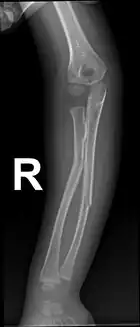

Greenstick fractures on X-ray.

Greenstick fractures

Projectional radiography is generally preferable.